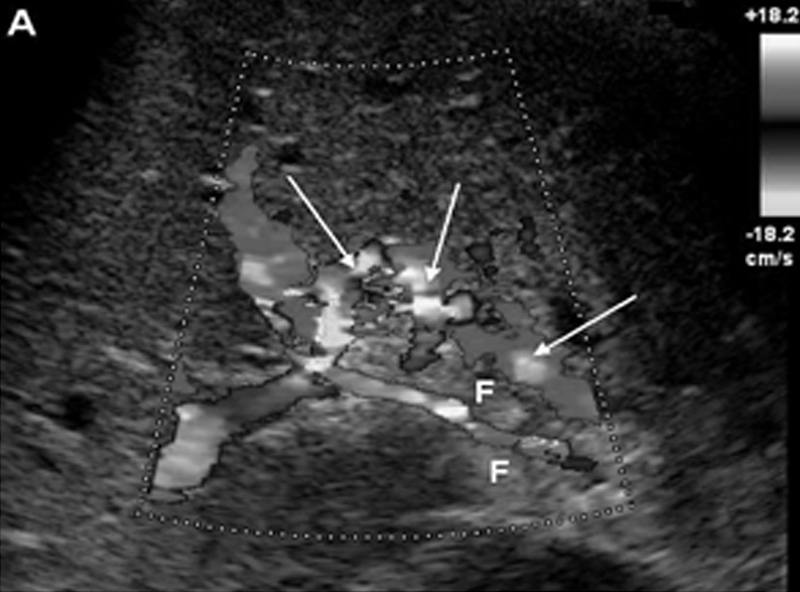

Основной маркер ХТВВ при УЗДГ, КТ и МР-исследованиях – это наличие портальной каверномы (рис. 4), представляющей собой сеть портопортальных коллатералей в воротах печени. Кроме того, наблюдаются спленомегалия, дефект (или отсутствие) контрастирования стола ВВ или фиброзный тяж на её месте; развитая сеть портопортальных и портосистемных коллатералей в области селезёнки, большого сальника и др.[15, 17, 18-20, 22, 24, 35, 40, 47, 57]

Рис.4. Ультразвуковая допплерогамма больного с хроническим тромбозом воротной вены: представлены сеть коллатеральных сосудов (стрелки) и фиброз (F) в области воротной вены. [35]